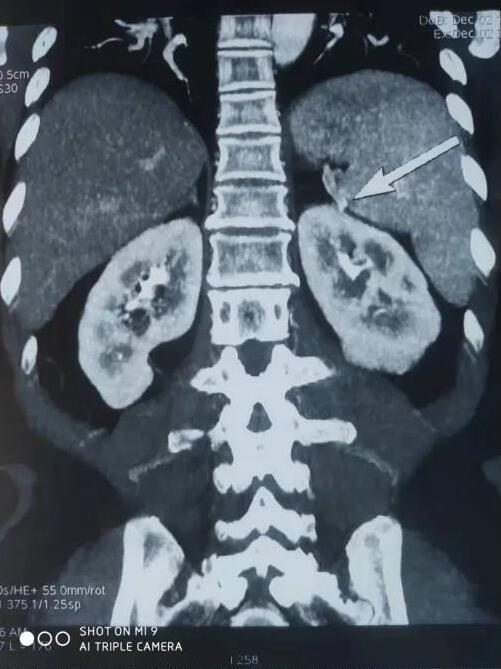

患者,女性,61岁,因体检发现左肾肿物一周收入院,入院后行全腹部增强CT检查回报:左肾下极肿瘤。大小48*47mmhg,肿瘤分期:T1bM0N0,肿瘤位于肾实质深部,上极紧贴肾门,各期影像显示患肾血供复杂:包括肾动脉、副肾动脉各一支。

变异血管分布如下:

第四腰椎椎前血管发出的侧支动脉一支

穿过后腹膜入肾上极变异动脉一支(来源于脾动脉)

肿瘤回流静脉一支(内有癌栓)